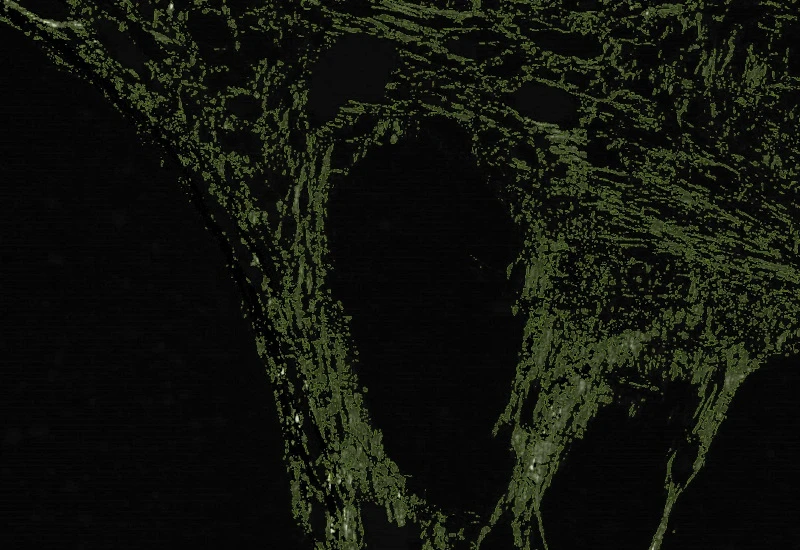

Sirius Red Polarized

Quantify collagen type I (red) and type III (green) fibers in Sirius Red–stained polarized images, measuring region area and the area of red, green, and overlapping (double-positive) fibers.

The Sirius Red Polarized App allows for quantification of collagen type I and type III based on Sirius Red Staining imaged with polarized light. It outputs the region area (µm2), the area of collagen type I = red fibres (µm2), collagen type III = green fibres (µm2) and overlapping fibres (µm2).

Image courtesy of Dr. Mortiz Uhlig, University Hospital RWTH Aachen

Detection of collagen type III